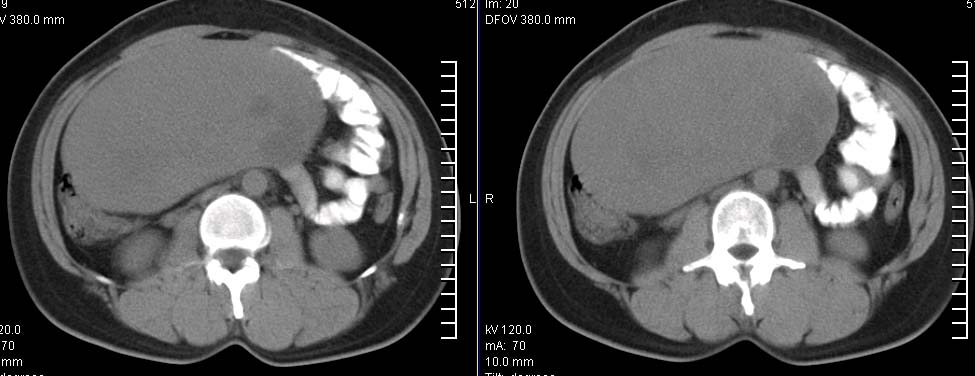

标题: CT9722:卵巢巨大占位,约10*18*21CM大小 [打印本页]

标题: CT9722:卵巢巨大占位,约10*18*21CM大小

卵巢巨大占位,约10*18*21cm大小

肿瘤的密度有点高.和子宫差不多?且和子宫相连呢?我考虑来源于子宫,子宫巨大子宫肌瘤可能性大!(局部有坏死?)

子宫肌瘤不除外哦。

肿瘤的密度有点高.和子宫差不多?且和子宫相连呢?我考虑来源于子宫,